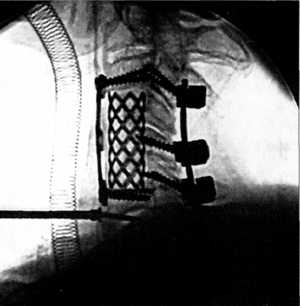

Рис. 3.6. Компрессионный перелом тела

С5 позвонка до и после операции. Стабилизация металлической конструкцией. |